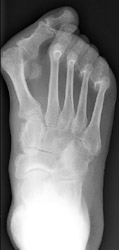

3. Differential diagnosis:

Radiographic changes characteristic of arthritis of Reiter's disease are identical

to those of psoriatic arthritis. However, the differences in distribution

between the two allows for more accurate diagnosis. Reiter's arthritis predominately

involves lower extremity, primarily feet, ankles, knees, and SI joints in

bilateral asymmetric distribution. Hands, hips, and spine are less frequently

involved.